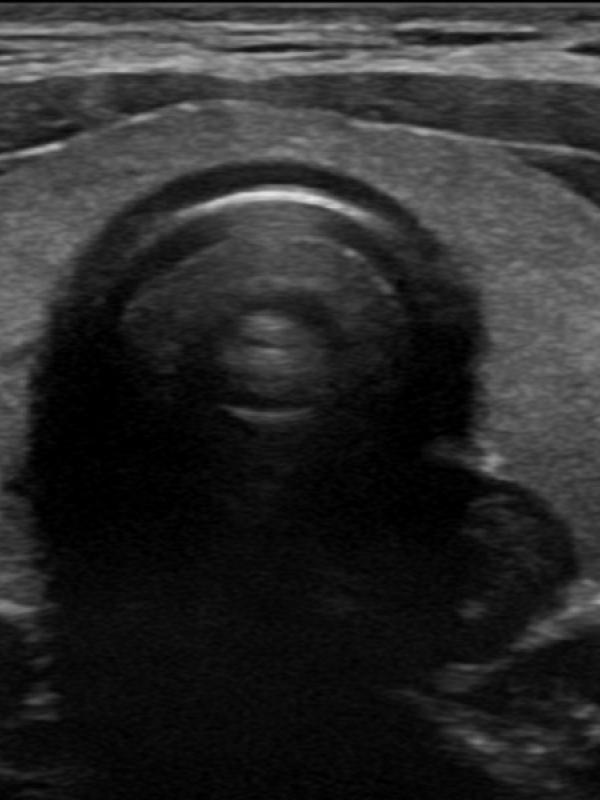

Thyroid ultrasound

Ultrasound an excellent diagnostic tool for thyroid evaluation. It is used to evaluate the size of the gland, texture, and evaluate for lesions. The most common reasons for a referring provider to order a thyroid ultrasound are for abnormal thyroid lab values or a suspected abnormality following a physical.